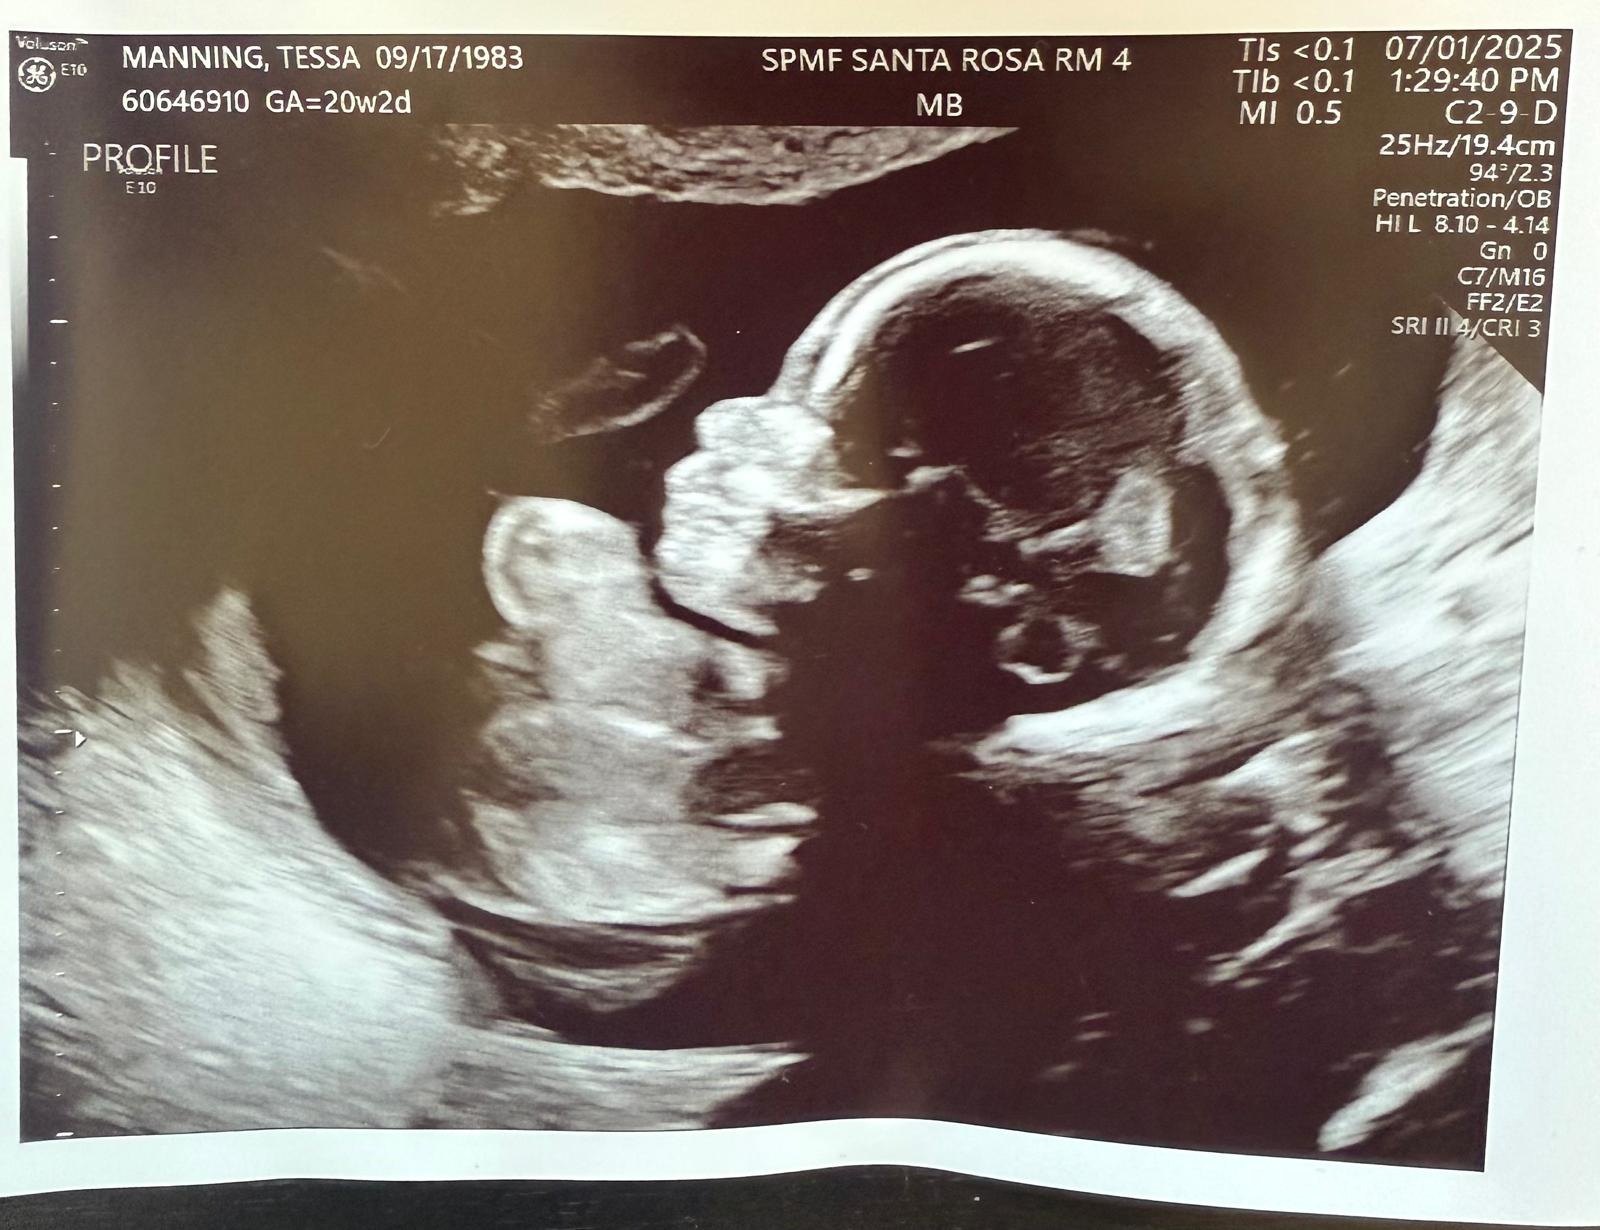

With 2nd baby boy on the way, Tessa went in for her 20 week ultrasound and they discovered she was already 2cm dilated with no cervical cap left.. babies feet were in the cervical canal..